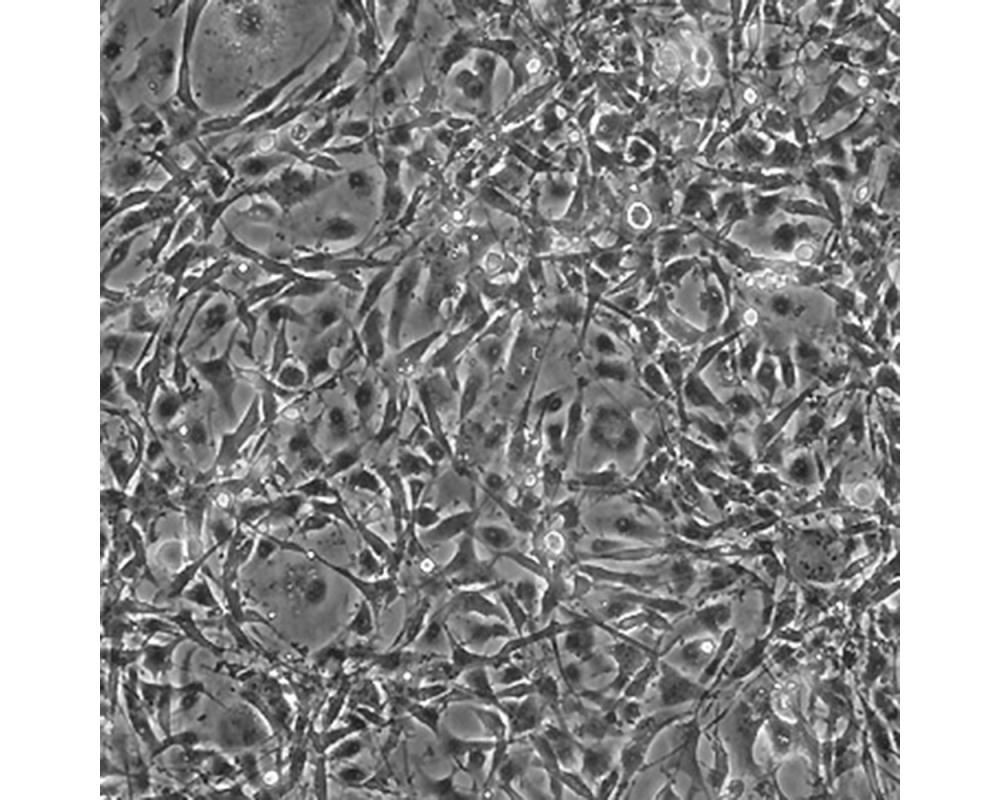

U-118 MG

中文名稱 人腦星形膠質母細胞瘤

組織來源 星形膠質母細胞瘤;男性

細胞種屬 Homo sapiens, human

生長特性 adherent

培養基 DMEM+10% FBS+1% P/S

形態特征 mixed

細胞描述 注意: 據報道來自不同個體的膠質母細胞瘤細胞株U-118 MG (HTB-15) 和 U-138 MG (HTB-16)有著一致的VNTR和相近的STR模式。 U-118 MG 和 U-138 MG細胞遺傳學上很相似并有至少六個衍生標記染色體。 這是1966年至1969年間J. Ponten和同事從惡性神經膠質瘤中構建的細胞株中的一株(其它包括ATCC HTB-14和 ATCC HTB-16 and ATCC HTB-17)。 1987年用BM-Cycline培養6周去除了支原體污染。